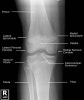

소아 무릎, 아래 다리의 X-ray2017-02-25카테고리 103원본 보기 Knee Paediatric Protocol : AP, Lateral Knee lateral view Knee AP view Tibia/Fibula AP/Lateral view ← 이전 글내족지 보행(In-toeing gait) : 아이가 안짱다리 모양의 걸음걸이를 보여요다음 글 →소아 발목의 X-ray같은 카테고리 글2017-02-26소아 발목의 X-ray2017-02-18소아의 골반, 고관절, 대퇴골의 X-ray2017-02-14손목 성장판 골단판 골절(Epiphysiolysis fracture)← 전체 글로 돌아가기